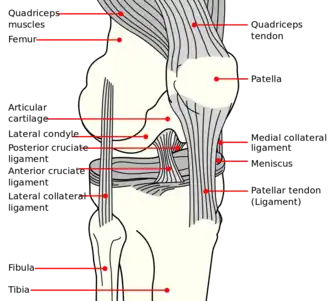

| Pellegrini-Stieda syndrome. Also visible is a fracture of the patella. |

Pellegrini–Stieda syndrome (also called Stieda disease and Köhler–Pellegrini–Stieda disease) is the ossification of the superior part of the medial collateral ligament of the knee. It is a common incidental finding on knee radiographs. It is named for the Italian surgeon A. Pellegrini (b. 1877) and the German surgeon A. Stieda (1869–1945).[1] While the eponym refers to Pellegrini and Stieda, the condition was first discovered by Köhler in 1903, before any namesakes. Pellegrini-Stieda combines the aforementioned radiographic findings and concomitant medial knee joint pain or restricted range of motion.[2]

Pellegrini-Stieda syndrome is an insult to the medial collateral ligament (MCL), causing damage and acute inflammation that sets into motion and delays ossification.[2] This insult is described as a macro trauma causing valgus stress with disruption of the MCL fibers. This condition is usually associated with sports activity.

The initial injury to the knee, whether resulting from macro- or repetitive microtrauma, leads to the same result: calcific ossification of the soft tissue structures surrounding the medial femoral condyle.[2] This sprain or tear in the medial collateral ligament leads to inflammation of the area. The bodies inflammatory response lead to an immune response to try to repair leading to an abnormal healing process. The abnormalities lead to a disposition of calcium at the tear site of the medial collateral ligament which over time hardens to form a bony mass called heterotrophic ossification. As healing continues, the fibrocartilage or other disorganized tissue becomes calcified, and over weeks to months, it ossifies, forming bone-like material at the MCL attachment site.[5]

Diagnosis is typically made on radiographs demonstrating the Pellegrini-Stieda syndrome sign accompanied by pain or restriction of range-of-motion of the knee joint.[2] Pellegrini-Stieda syndrome sign is typically described by a longitudinally linear opacity, which is a process that is describes characteristic of calcification in the soft tissue located medial to the medial femoral condyle.[2] This calcification seen on imaging represents the ossification of the medial collateral ligament, which typically does not develop until approximately three weeks after the initial injury.[2]It is important to note to distinguish this radiographic finding from that of a medial femoral condyle avulsion fracture, which is an injury in which a pulling force of a tendon or ligament fractures away a piece of the bone from its attachment site.[2]